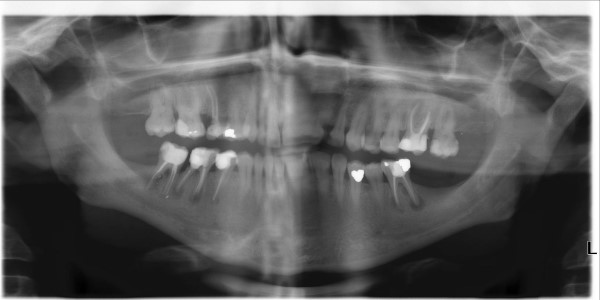

De kaakoverzichtsfoto, oftwel Orthopantomogram (OPD), wordt gemaakt om uw kaakgewricht te beoordelen. Hiermee kunnen we ontsteking(en) aan uw wortelpunt(en) ontdekken, wortelresten analyseren, de ligging van uw verstandskiezen beoordelen en bij de jeugd bekijken of alle volwassen tanden en kiezen aanwezig zijn.